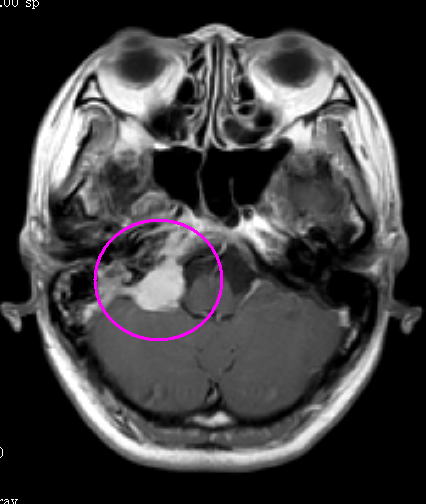

中咽頭癌 Ct Mri検査 がん 腫瘍 ピーチクパープル Yahoo ブログ

9回目pet ct Mri検査と血糖値 仕事をしながら中咽頭癌と闘う美容

2 中咽頭のct Mri 耳鼻咽喉科 頭頸部外科 67巻11号 医書 Jp